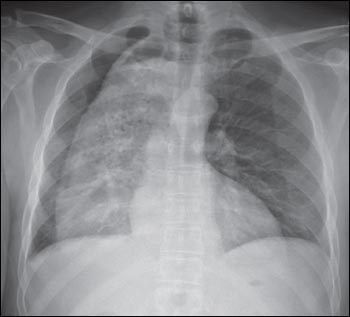

Results of laboratory studies were normal. A chest radiograph showed a markedly dilated esophagus and a possible small pleural effusion on the right side; no necrotic debris or undigested food material was noted. The cardiac silhouette showed normal borders. The trachea was midline.